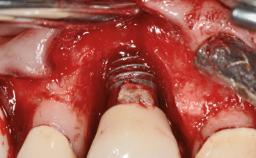

A 77-year-old male patient was referred for the management of frequent and repeated acrylic fracture of his existing mandibular fixed full-arch implant-supported metal/acrylic prosthesis. He also complained about softtissue soreness and the lack of retention and stability of his maxillary removable partial metal/acrylic prosthesis. Both prostheses had been delivered two years previously as part of his full-mouth rehabilitation (caries, tooth wear, tooth fracture). His medical history revealed high blood pressure, controlled with the use of antihypertensive medication.

Defining Characteristics Fully edentulous lower jaw to be rehabilitated with two or more implants

Modality > 4 implants, extending to mental nerve region